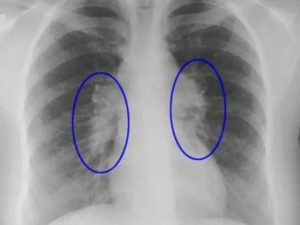

Узловые образования, как правило, обнаруживаются при рентгенологическом обследовании или компьютерной томографии. Они представляют собой сферические тени или уплотнения различных размеров.

При этом обращают внимание на структуру узелка и окружающих тканей (кальцификаты, липидные включения, тяжи), количество очагов и их локализацию.

Все обнаруженные тени в легких принято считать потенциально злокачественными до тех пор, пока не будет доказано обратное. К признакам доброкачественности можно отнести кальцификаты и отсутствие роста на протяжении 2 и более лет при наблюдении в динамике. Благоприятными симптомами также являются гладкие края, равномерность, правильная форма образований.

Доброкачественные узелки в легких обычно имеют гладкие края и более равномерный цвет по всей поверхности. Они более правильной формы, чем раковые узелки. В большинстве случаев для проверки скорости роста, формы и других характеристик опухоли (к примеру, кальцификации), достаточно рентгена грудной клетки или компьютерной томографии (КТ).